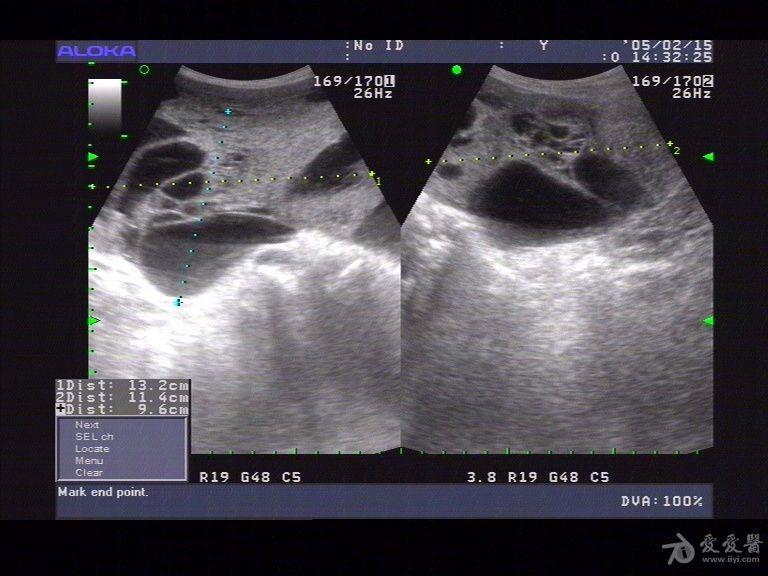

典型卵巢癌超声图像

粘液性囊腺癌(囊实性)声像图11-4-10 卵巢低分化腺癌声像图11-4-11